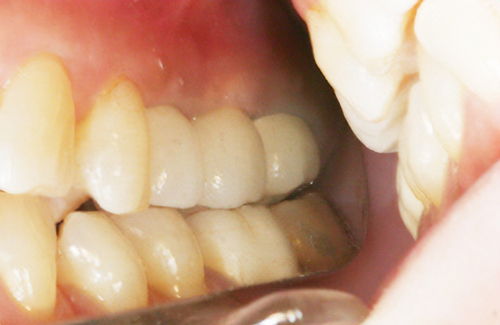

• 審美面も機能面でも回復

インプラントとは、失ってしまった歯の代用として、人工歯根=インプラントを埋め込む方法です。この人工歯根の上に、セラミックなどの被せ物を装着することで、審美面も機能面でも回復する方法です。

• 術前

土台